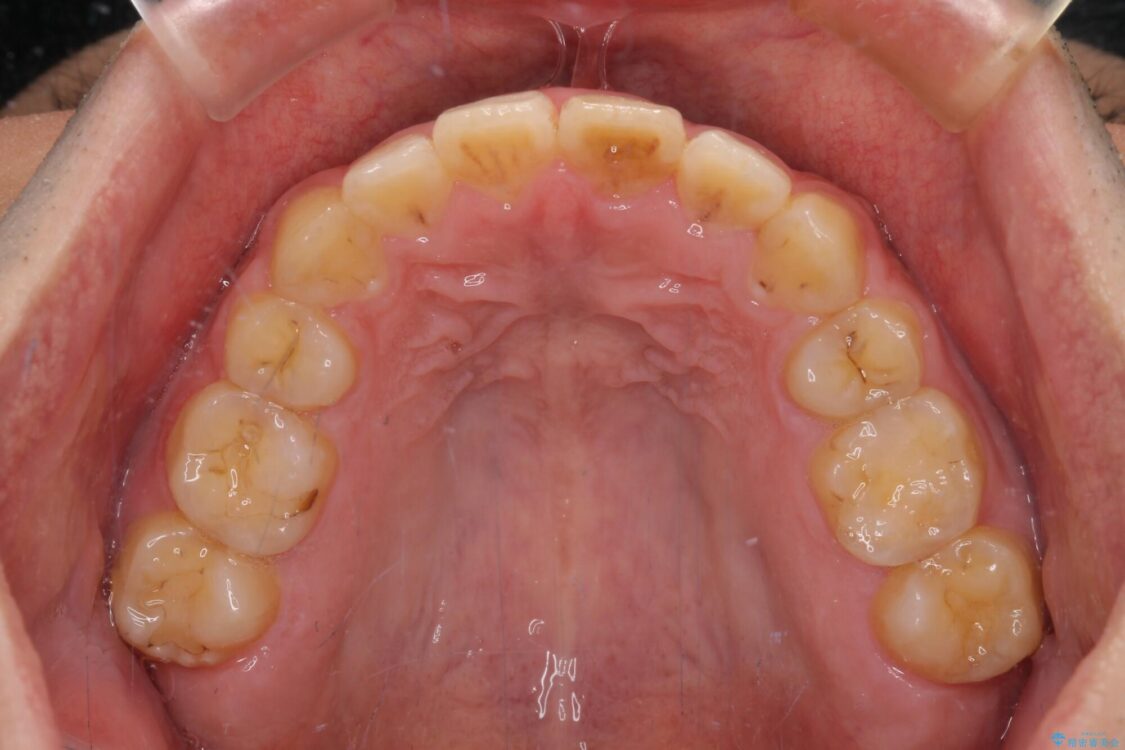

高校時代に行った抜歯矯正が後戻りをしたとのことで来院された患者様です。

治療前

• 後戻りでデコボコの前歯 インビザライン矯正治療 治療前画像